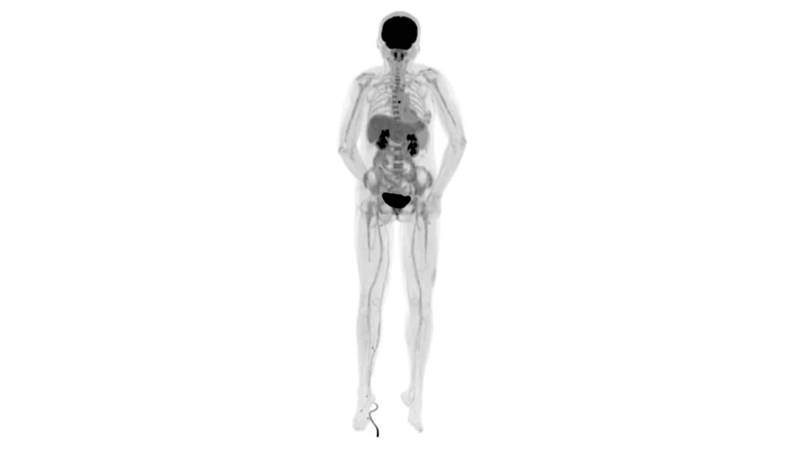

uExplorer探索者不再局限于傳統(tǒng)靜態(tài)代謝過程3D成像,而是在此基礎(chǔ)上新增一個維度——時間,從而實現(xiàn)4D全景成像。

注射總劑量為7.8mCi,14分鐘全身采集時間,在擁有超高靈敏度與超高分辨率的uEXPLORER上,即可得到展示顯示人體諸多精細結(jié)構(gòu)的高清三維圖像。